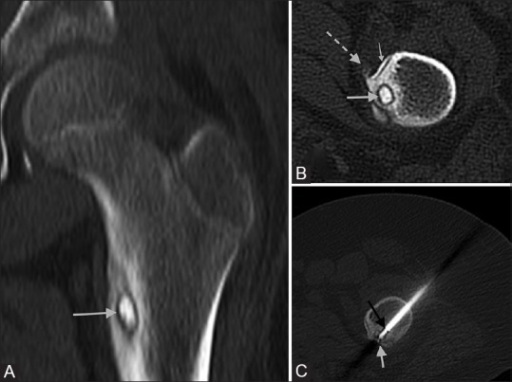

Axial CT scan of the proximal femur demonstrating a classic osteoid osteoma. The central lucent nidus (<1.5cm) is visible with surrounding reactive sclerosis. The nidus may show central calcification. The cortical location with focal thickening is characteristic. Bone scan shows intense uptake (double-density sign). Treatment options include NSAID trial, CT-guided radiofrequency ablation, or surgical excision.